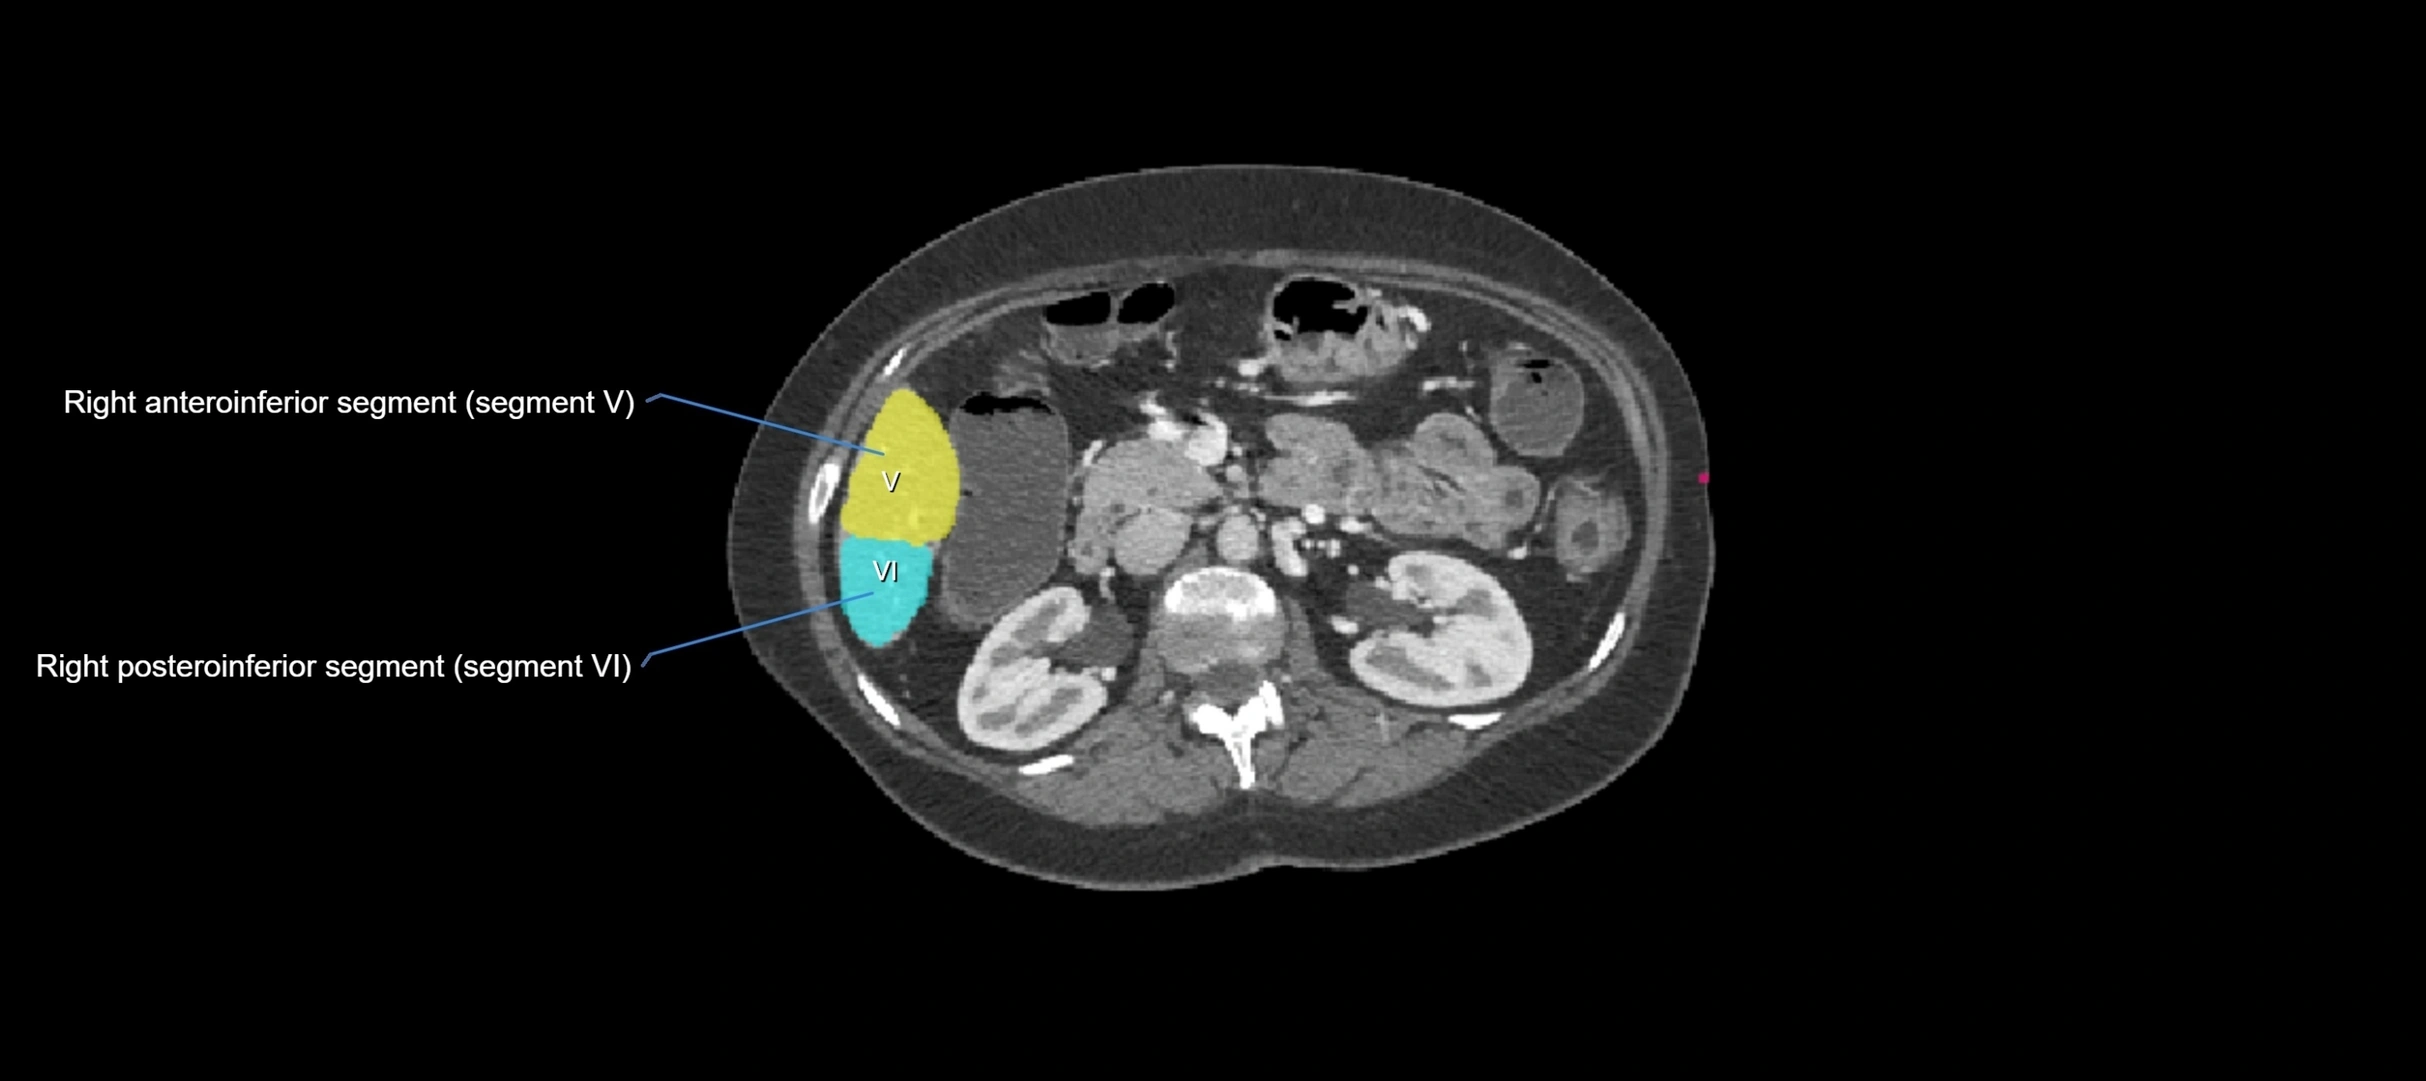

CT Appearance

CT Pre-Contrast:

• Caudate lobe appears as a soft-tissue density, isodense to the rest of the liver

• Enlargement may be appreciated in cirrhosis or Budd–Chiari syndrome

CT Post-Contrast:

• Homogeneous enhancement in the portal venous phase, similar to rest of liver

• Independent venous drainage into the IVC may be visualized

• Lesions follow characteristic CT enhancement patterns (HCC: arterial hyperenhancement with washout; hemangiomas: peripheral nodular enhancement with centripetal fill-in)

CT Venous Phase (functional significance):

• Caudate lobe often enhances relatively more than other lobes in Budd–Chiari syndrome, due to preserved venous outflow

CT Image

image